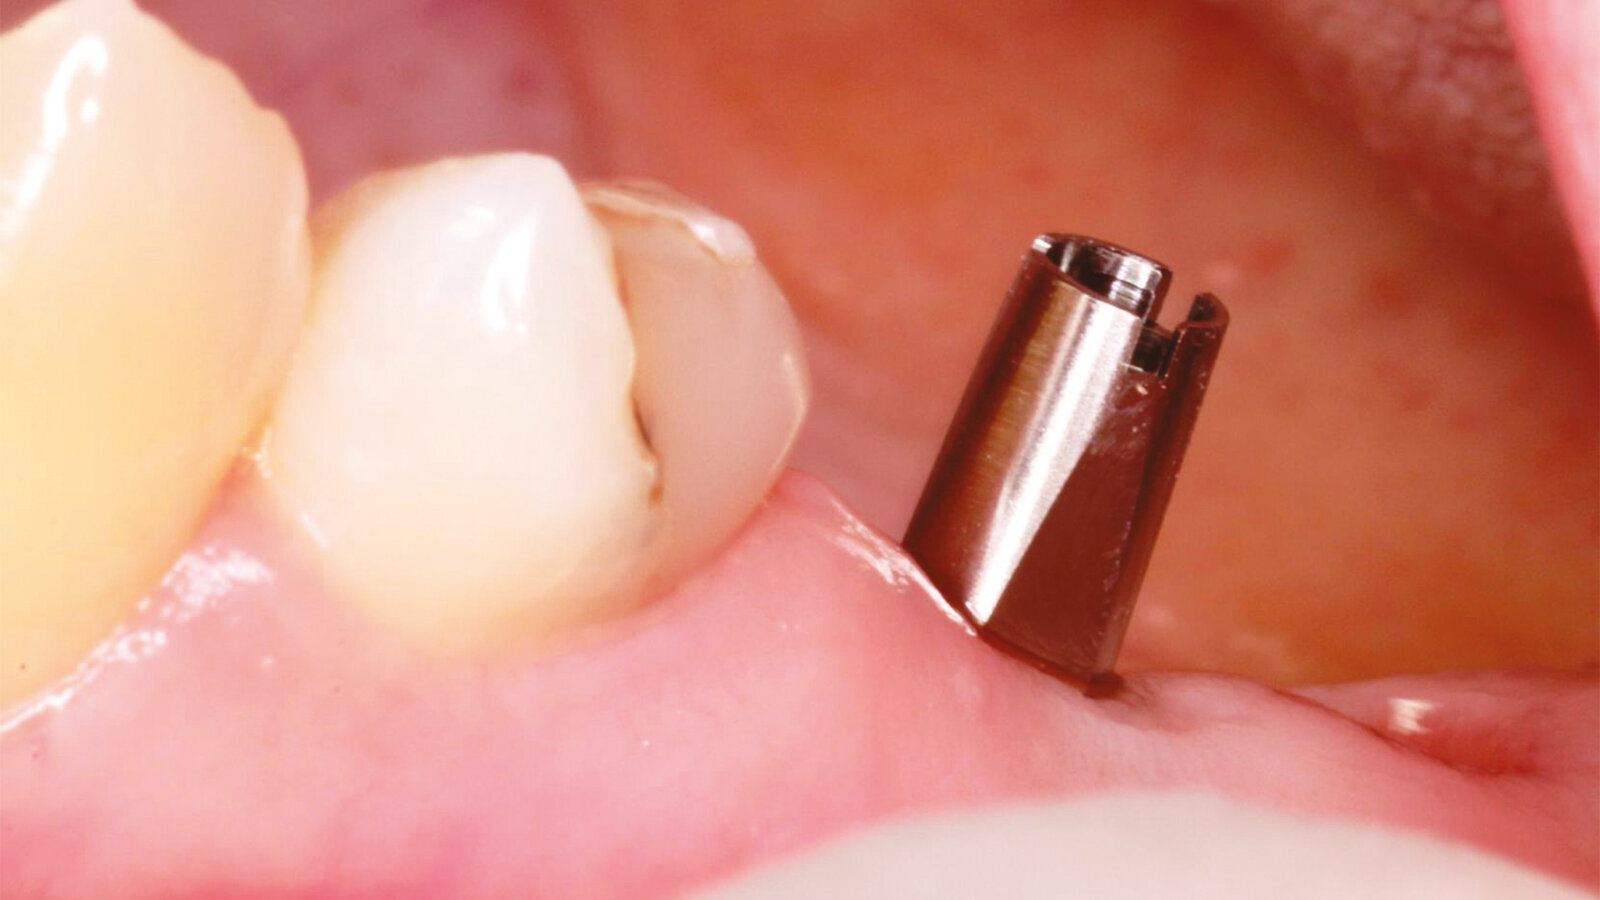

Fig.7: Axiom concept for healing cap selection to form transmucosal passage for excellent final aesthetics.

A 43-year-old female presents with missing premolar and molar upper right side (#15,16) and missing premolar upper left (#25). These teeth have been missing for 15+ years. A flapless approach was selected to minimize trauma and to facilitate quick healing. The Axiom Concept was utilized to create an emergence profile that would be difficult to detect from the natural dentition.